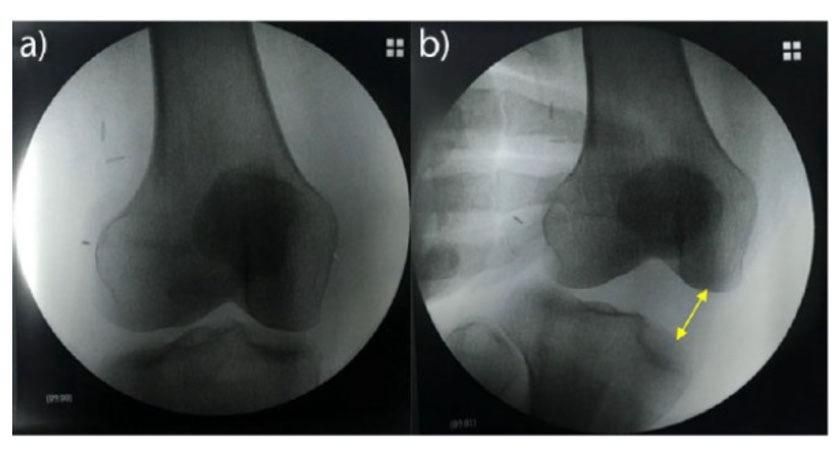

看懂【内侧副韧带】内侧副韧带,膝关节内侧稳定的核心。抵抗膝关节外翻应力,限制胫骨外旋。